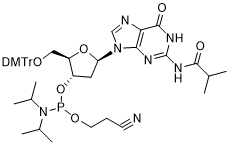

馬鞍山致研生物醫(yī)藥科技有限公司成立于馬鞍山市鄭浦港新區(qū)現(xiàn)代產(chǎn)業(yè)園。公司專(zhuān)注于生物小分子、醫(yī)藥中間體相關(guān)產(chǎn)品的研發(fā)和生產(chǎn),產(chǎn)品主要包括DNA亞磷酰胺單體、RNA亞磷酰胺單體、特殊單體以及按照客戶(hù)要求定制的RNA和DNA,并且公司提供定制合成等方面的研究服...

馬鞍山致研生物醫(yī)藥科技有限公司成立于馬鞍山市鄭浦港新區(qū)現(xiàn)代產(chǎn)業(yè)園。公司專(zhuān)注于生物小分子、醫(yī)藥中間體相關(guān)產(chǎn)品的研發(fā)和生產(chǎn),產(chǎn)品主要包括DNA亞磷酰胺單體、RNA亞磷酰胺單體、特殊單體以及按照客戶(hù)要求定制的RNA和DNA,并且公司提供定制合成等方面的研究服...